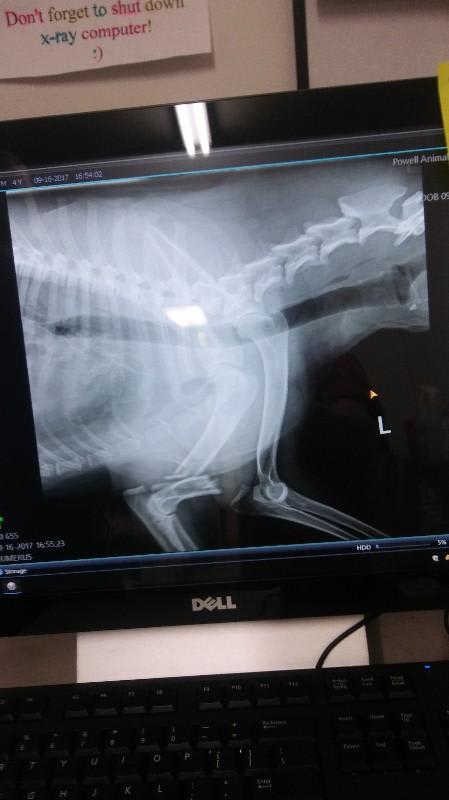

My dog has a broken elbow. What are the treatment options?

Would a break in front right elbow require amputation, or will a splint, cast, or hobble possibly work?

That looks like a pretty nasty fracture. My first recommendation would be orthopedic surgery. The surgeon may recommend plates or other devices to get the bone back in alignment so that it can heal. If that is not an option in your area, then amputation would be my next recommendation. Due to the location, a cast or splint will not provide enough stabilization to allow the edges of the bone to knit back together. If the bones can be re-aligned, a hobble can be attempted, but the failure rate is quite high.

Oh goodness. That looks like a bad break. Was there a big trauma? Most fractures of the humerus require surgical stabilization. Splints and casts usually just act as a fulcrum and don't really help. Amputation isn't wrong, but surgical stabilization would be my first choice. I hope this was helpful!